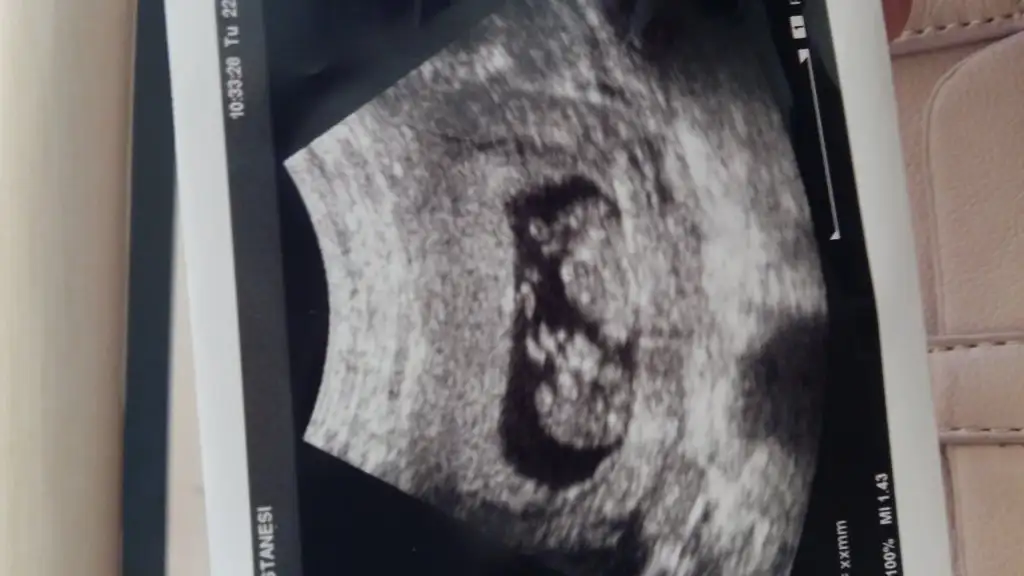

herkese merhaba bugün doktor kontrolünden aldığım ultrason görüntüsüyle geldim buraya,8 haftalık olduğunu söyledi doktorum. ben de merak ediyorum açıkçası sizce tahminleriniz nelerdir kız mı erkek mi? benim içime kız doğuyor sürekli kız bebek rüyaları görüyorum :)

Ben anlamadim. Benimki Erkek mi kiz mi 13haftalikken erkek demişti doktor 15 haftalikken %90 kiz dedi yardımcı olur musunuz 7haftalik goruntusu